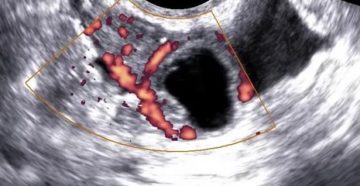

Киста в яичнике после стимуляции овуляции: виды кист, причины возникновения, диагностика, лечение заболевания Киста яичника…

Беременность при кисте желтого тела: возможно ли это Киста желтого тела – это частый гинекологический…